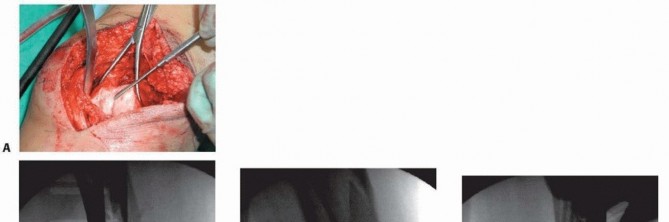

### TECH FIG 2 • AP radiograph (A) and scanogram (B) showing that length was reestablished with the external fixator. The rotation should be checked once again before locking the external fixator construct, as described earlier under Positioning. The same technique should be performed under sterile conditions. Varus-valgus alignment should be assessed before final tightening as well. This can be done by using the Bovie cord intraoperatively and assessing the mechanical axis of the limb by fluoroscopically evaluating from the hip to the ankle with the cord centered at the femoral head all the way to the ankle. The point at which the cord crosses the knee allows one to judge the varus-valgus alignment. 2. ## Open Reduction and Internal Fixation of the Distal Femur with Locking Plates (Type C Fractures) This technique can be used regardless of the locking plate system used. Each system's technique guide should be reviewed before use as each system has its own idiosyncrasies. Variations in plate application as well as reduction tools and techniques are unique to each system. The temporary external fixator is prepared using a “doubledouble” technique. The fixator is first prepared with a Betadine “scrub” (7.5% povidone-iodine) solution followed by a Betadine “paint” (10% povidone-iodine) solution (Beta-Beta preparation), followed by the extremity with a second Beta-Beta preparation. The surgeon then does an alcohol preparation, followed by iodine for the fixator, followed by alcohol and iodine on the skin. This has been successful in our practice and allows for maintenance of traction during the preparation and aids in the actual surgery, functioning as a femoral distractor. (Chlorhexidine is used in iodine- allergic patients.) An alternative is to completely remove the fixator components, except the pins, and wash, sterilize, and then reassemble the fixator on the patient after the leg has been prepared. If there is no temporary bridging external fixator, the metaphyseal component of the fracture can be reduced and brought out to length with a femoral distractor, a temporary simple external fixator, or manual traction if adequate help is available. Rotation of the proximal segment can be manipulated with the device used. 480 ### Midline Approach with an Extended Lateral Parapatellar Arthrotomy A straight incision is made directly anterior about 5 cm proximal to the superior pole of the patella and distally to the level of the tibia tubercle ( TECH FIG 3A). The lateral skin flap is developed to allow for a lateral parapatellar arthrotomy ( TECH FIG 3B). The arthrotomy is performed, ensuring a cuff of tissue on the lateral aspect of the patella for repair as well as medially on the quadriceps ( TECH FIG 3C). The patella can be subluxed medially or inverted with knee flexion to allow exposure of the condyles ( TECH FIG 3D). Additionally, a blunt Hohmann retractor can be placed on the medial side at the level of the condyle to retract the patella. The capsule is subperiosteally elevated off the lateral femoral condyle to allow for placement of the plate. The lateral collateral ligament is preserved because the dissection is limited to the anterior two-thirds of the lateral femoral condyle and plate placement is usually proximal to the lateral epicondyle. The medial side in the metaphyseal region is left undisturbed as much as possible.

TECH FIG 3 • Patient with grade II open distal femur fracture (also shown in FIGS 5D-F, 6B, and 7). A. Straight midline incision. B. Lateral skin flap is developed. C. Arthrotomy is started and then extended proximally into the quad tendon (dashed line). D. The arthrotomy is completed and the condyles are visualized with medial subluxation of the patella. ### Reduction of the Articular Surface The joint is evaluated to determine comminution. Joint reconstruction is then performed with direct reduction. Each condyle is fully assessed first for smaller fracture fragments, with the goal of restoring each condyle anatomically. Small-diameter screws ( <3.0 mm) may be used and can be countersunk underneath the articular surface. Large coronal fracture fragments are best treated with countersunk 3.5- to 4.5-mm lag-type screws. We use headless screws. Once each condyle is thought to be restored, or if a simple fracture pattern is present, the condyles should be reduced to each other using a large, pointed reduction forceps ( TECH FIG 4A-C). Each fragment can be rotated relative to another; this must be addressed as discussed before. The best way to assess this is under direct visualization and evaluating the reduction at the trochlear region of the patellofemoral joint. Additionally, preoperative evaluation assessing the lateral radiograph can guide the surgeon. Intraoperative fluoroscopy to reassess the lateral view is also useful. Temporary Kirschner wires or the guide pins for the locking screws for the plate can be used for additional stabilization of the two condyles ( TECH FIG 4D). 481